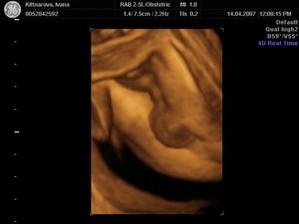

Někdy kolem 12. července by se nám mělo narodit naše první miminko. Všichni se už moc těšíme :o)

Podle ultrazvuku ve 20.tt by to měl být chlapeček.